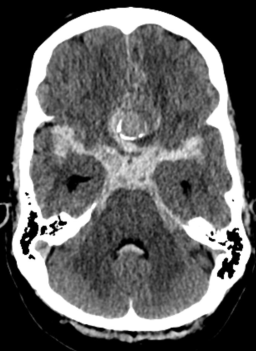

Vuotava aneurysma TT-kuvassa

Subaraknoidalblödning orsakad av ett rupturerat hjärnaneurysm.